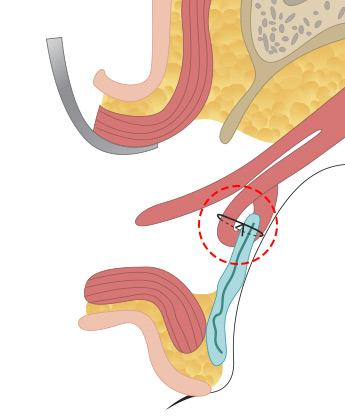

<p class="txt_1" data-delay="0.4" data-direction="bottom">

근육과 근막이 안검판이라는 조직에 붙어 있는데 안검하수의 정도에 따라서 경미한 경우는 근막의 길이를 축소해서 다시 붙여주는 상안검거근막 수술을 해주고, <br>

중증도의 경우 뮬러 근육을 당겨서 안검판에 고정하는 수술을 하고 중증인 경우에는 상안검거근을 아래로 당겨서 축소해주는 수술을 합니다.

수술 방법

근육과 근막이 안검판이라는 조직에 붙어 있는데 안검하수의 정도에 따라서 경미한 경우는 근막의 길이를 축소해서 다시 붙여주는 상안검거근막 수술을 해주고,

중증도의 경우 뮬러 근육을 당겨서 안검판에 고정하는 수술을 하고 중증인 경우에는 상안검거근을 아래로 당겨서 축소해주는 수술을 합니다.

올림근 널힘줄 중첩술

올림근 널힘줄 중첩술 -

뮬러근 중첩술

뮬러근 중첩술 -

뮬러근 전진술

뮬러근 전진술 -

뮬러근과 올림근, 널힘줄을

뮬러근과 올림근, 널힘줄을

동시에 전진술로 교정